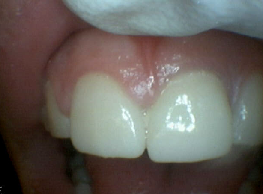

Anterior Wear corrected with Hybrid Resins